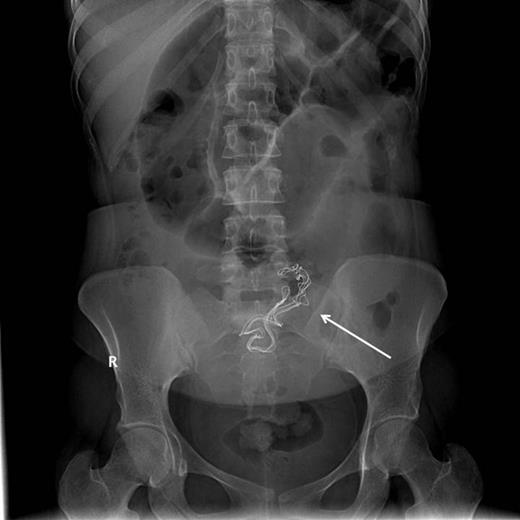

Upon admission, she was afebrile, vitally stable, and her abdomen was distended and tympanic. Bowel sounds were increased in frequency and pitch. Digital rectal examination showed normal-colored stool. Laboratory investigations showed a white blood cell count of 10 700 cells/ml and a sodium level of 123 mmol/l, while other biochemical parameters were within normal limits. Abdominal roentography revealed dilated small intestinal loops with a finding of a radio-opaque density in the abdomen (Fig. 2). A diagnosis of small intestinal obstruction most likely caused by retained surgical sponge was made. On abdominal exploration, the small intestine was dilated down to the ileum with an intraluminal mobile mass felt in the distal ileum (Fig. 3). Before proceeding for mass removal, at around 80 cm from the duodenojejunal junction, there were two adjacent segments of the jejunum adherent to each other and both were adherent to the peritoneal wall by fibrous adhesions. Consequently, adhenolysis, enterotomy and removal of the mass, which was manually pushed there (Fig. 4), followed by resection and anastomosis of the compromised jejunal segment, were achieved. The foreign body was found to be retained surgical sponge (Fig. 5). However, apart from the isolated area of adhesion, exploration of the rest of the abdominal cavity did not show any lesions in the peritoneal cavity or perforation or fistula or pelvic collection. The authors concluded that the transluminal migration of the sponge most likely occurred from that adherent part of the jejunum. The postoperative period was uneventful and the patient was discharged on the seventh day of her hospitalization in good condition.

Intraluminal foreign body visible at the ileum with an intact normal wall (forceps).